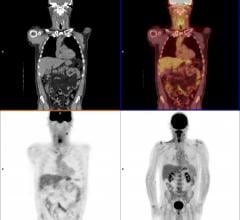

June 20, 2017 — Simultaneous injections of the radiopharmaceuticals fluorine-18 fluorodeoxyglucose (18F-FDG) and 18F ...